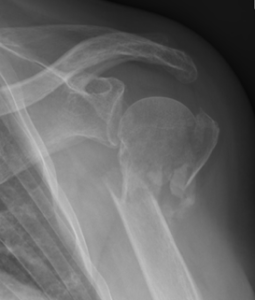

Schouder uit de kom (schouder(sub)luxatie)

Als de schouder gedeeltelijk uit de kom schiet (subluxatie) of helemaal uit de kom is (luxatie), worden de banden en kapsels in de schouder uitgerekt. Ook omliggende weefsels als spieren en banden beschadigen hierdoor. Omdat ze hierdoor niet meer in staat zijn om de kop van de bovenarm goed in de kom te houden, voelt de schouder instabiel. U kunt heftige pijnscheuten voelen. Ook kunt u het gevoel hebben dat de kop opnieuw uit de kom schiet. Vaak is er ook een stekende pijn aan de voorkant van de schouder. Vooral als u bovenhands kracht zet. Daarna blijft vaak een zeurende pijn achter. Zie voor meer informatie onze folder over schouderinstabiliteit.